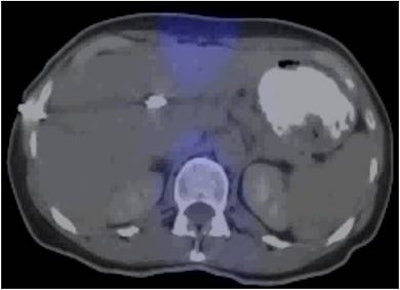

| The 3D VIBE MR image (above) shows the difference in data acquired compared to CT with stereotactic body radiation therapy (below). All images courtesy of Dr. John Mikell. |

![]() |